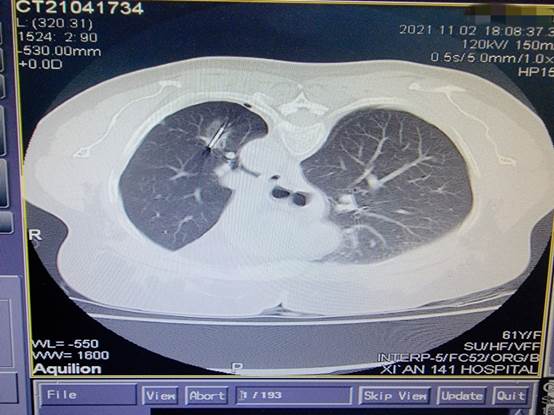

来自商洛市61岁的刘女士2年余前因左肺癌于我院行“胸腔镜左肺上叶癌根治术”,10天前复查行胸部CT发现左肺下叶结节,进一步行PET/CT示:左肺下叶结节,核素摄取异常,考虑转移癌。患者慕名来到付军科主任领衔的东院区胸外科就诊,付军科主任仔细查阅患者既往病历资料,临床诊断为转移结节,由于2年前已经实施肺叶切除术,经多学科讨论后决定给患者行肺结节微波消融术。11月2日下午,在医学影像科协助下,东院区胸外科团队成功开展了东院首例肺结节微波消融术,整个治疗过程非常顺利,患者无明显不适及并发症发生,术后复查胸部CT显示微波消融范围理想,病灶位于消融靶心。